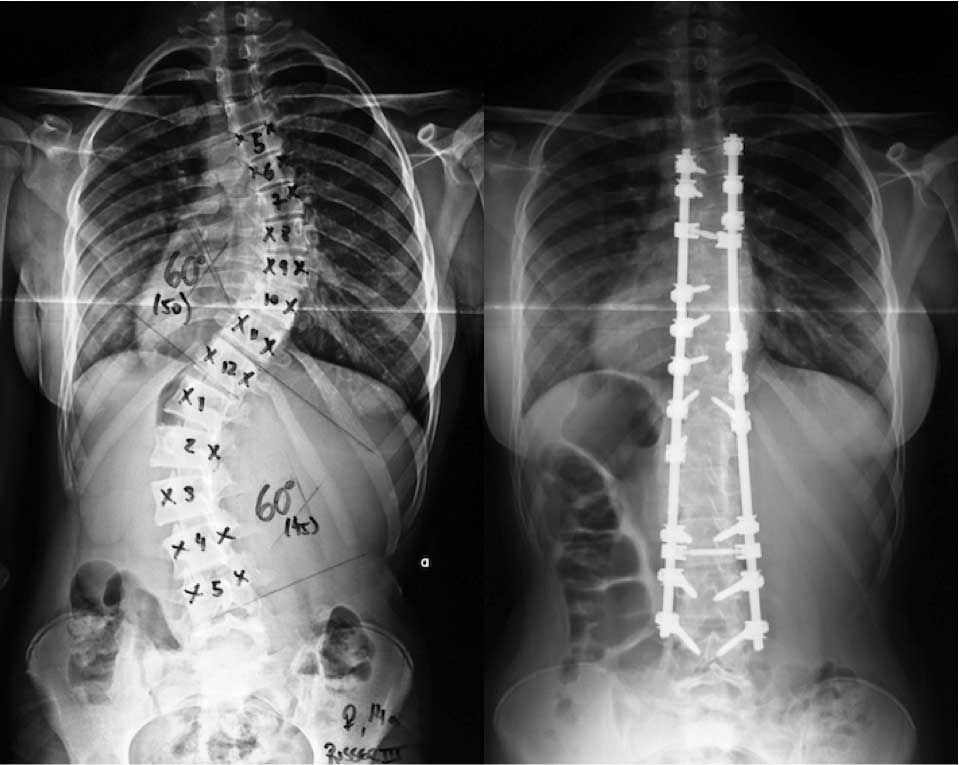

Pacientes que possuem um quadro progressivo da doença e curvaturas mais graves (acima de 50 graus) geralmente são candidatos à realização da cirurgia de escoliose.

Em adolescentes e adultos, o procedimento padrão é a correção da curva com artrodese (fusão óssea). Ela é necessária para manter a estabilidade e rigidez da coluna após a cirurgia.

Para isso é usada uma combinação de implantes metálicos na coluna (parafusos, hastes, etc) e enxerto ósseo, alinhando e estabilizando as vértebras da coluna através da fixação de parafusos ligados por hastes longitudinais, formando um bloco único que além de corrigir a deformidade, evita uma nova deformidade naquele segmento.

Com exames específicos, é possível medir o grau de correção conforme a flexibilidade da inclinação apresentada nas radiografias pré-operatórias. Geralmente, quanto maior a flexibilidade, maior o grau de correção. Escolioses em pacientes mais jovens costumam ser mais flexíveis, permitindo maior correção.